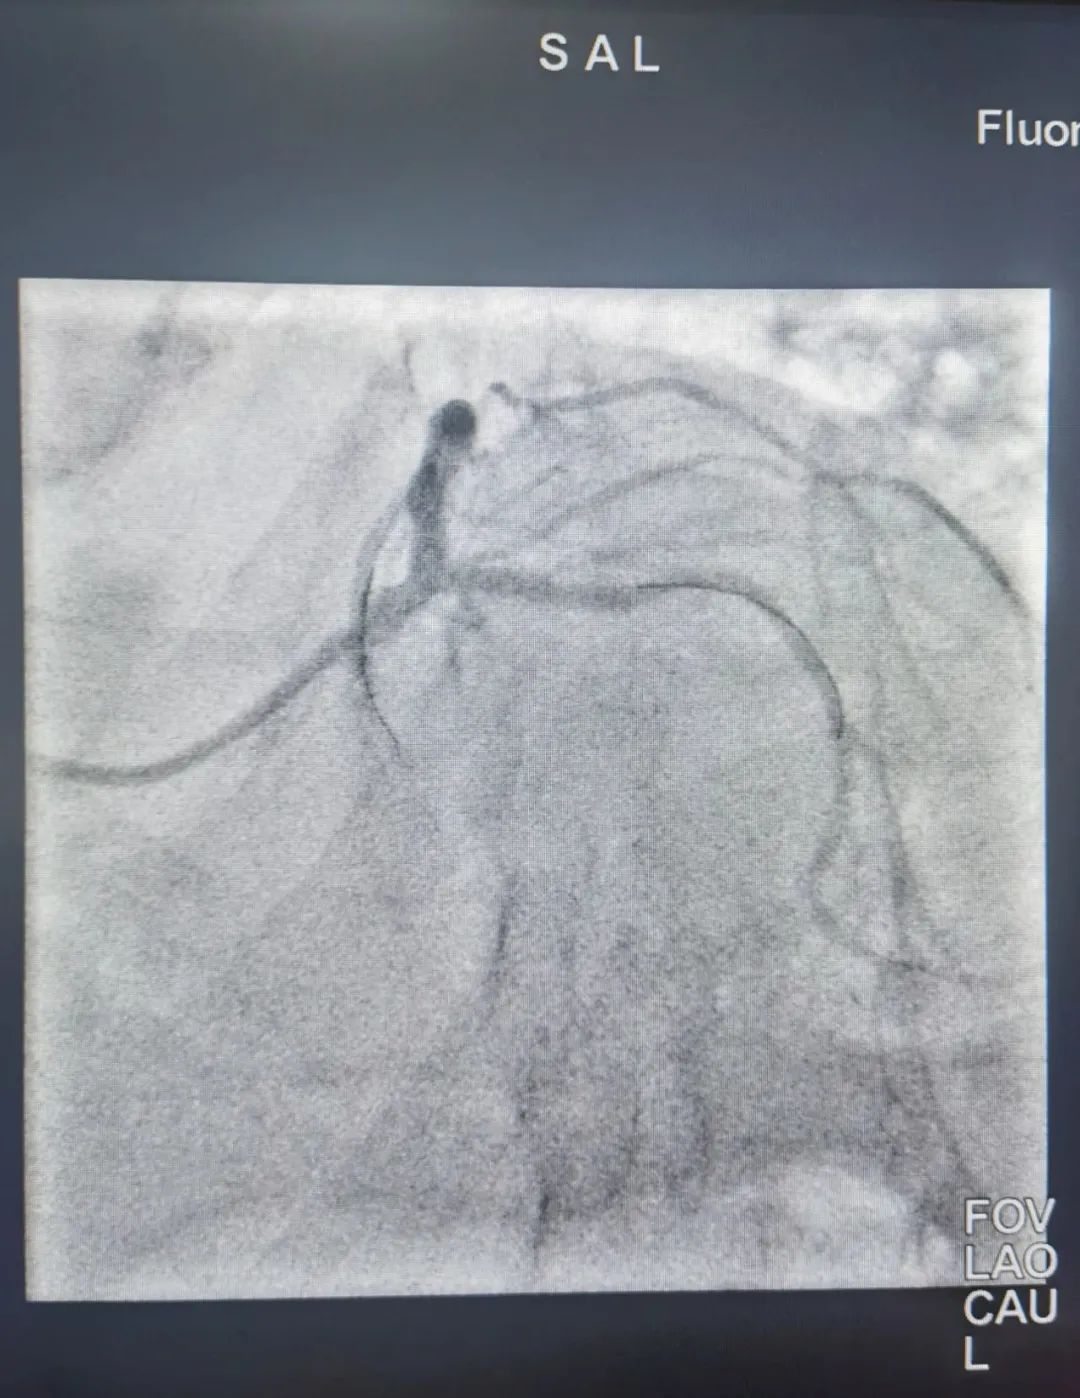

手术后血管显影图况

手术后血管显影图况

术后第2天,患者即成功撤除气管插管、ECMO治疗。术后第3天即转入普通病房。如今,老黄心绞痛症状完全缓解,复查心脏彩超左室射血分数38%,明显上升,病情好转后顺利出院。